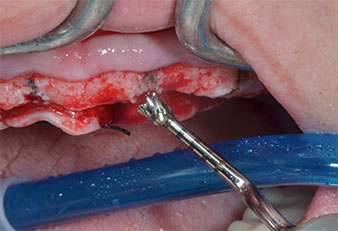

Motor de implantes (Implantmed)

Fig. 5: El diámetro final se logró con los insertos Piezomed I3A/I3P. En el caso de los implantes de 10 mm de las posiciones 11 y 21, los sitios se finalizaron con una fresa rotatoria de 3,5 mm en un motor de implantes (Implantmed).